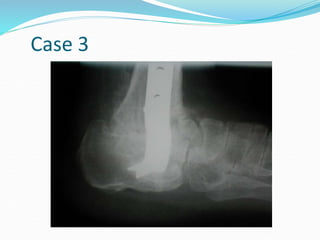

Case 3